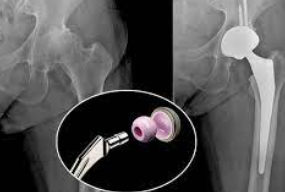

인공 관절 수술은 관절의 퇴행성 변화, 외상, 또는 다른 질환으로 인해 손상된 관절을 인공적인 재료로 만든 관절로 교체하는 의료 절차입니다. 이 수술은 주로 무릎, 고관절, 어깨 관절 등에 적용되며, 환자의 삶의 질을 향상시키고 통증을 감소시키는 데 목적이 있습니다.

인공 관절 수술의 종류는 크게 두 가지로 나뉩니다: 전치환술과 부분치환술입니다. 전치환술은 손상된 관절 전체를 인공 관절로 교체하는 방법이며, 부분치환술은 손상된 관절의 일부만을 교체하는 방법입니다. 환자의 상태와 필요에 따라 적절한 수술 방법이 선택됩니다.

전치환술은 관절의 변형이 심하거나 손상 부위가 넓은 경우에 주로 사용됩니다. 이 수술은 관절의 안쪽과 바깥쪽 모두를 인공 관절로 바꿔줌으로써, 통증을 줄이고 관절의 기능을 회복시키는 데 도움을 줍니다.